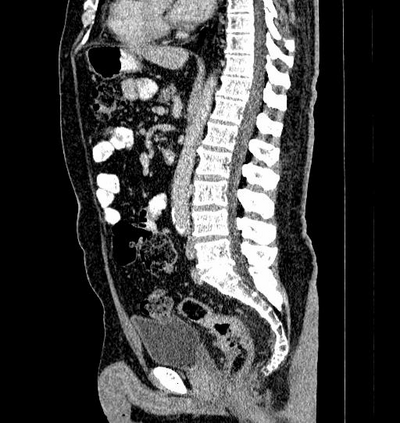

Due to the constraints of the imaging device and high cost in operation time, computer tomography (CT) scans are usually acquired with low intra-slice resolution. Improving the intra-slice resolution is beneficial to the disease diagnosis for both human experts and computer-aided systems. To this end, this paper builds a novel medical slice synthesis to increase the between-slice resolution. Considering that the ground-truth intermediate medical slices are always absent in clinical practice, we introduce the incremental cross-view mutual distillation strategy to accomplish this task in the self-supervised learning manner. Specifically, we model this problem from three different views: slice-wise interpolation from axial view and pixel-wise interpolation from coronal and sagittal views. Under this circumstance, the models learned from different views can distill valuable knowledge to guide the learning processes of each other. We can repeat this process to make the models synthesize intermediate slice data with increasing inter-slice resolution. To demonstrate the effectiveness of the proposed approach, we conduct comprehensive experiments on a large-scale CT dataset. Quantitative and qualitative comparison results show that our method outperforms state-of-the-art algorithms by clear margins.